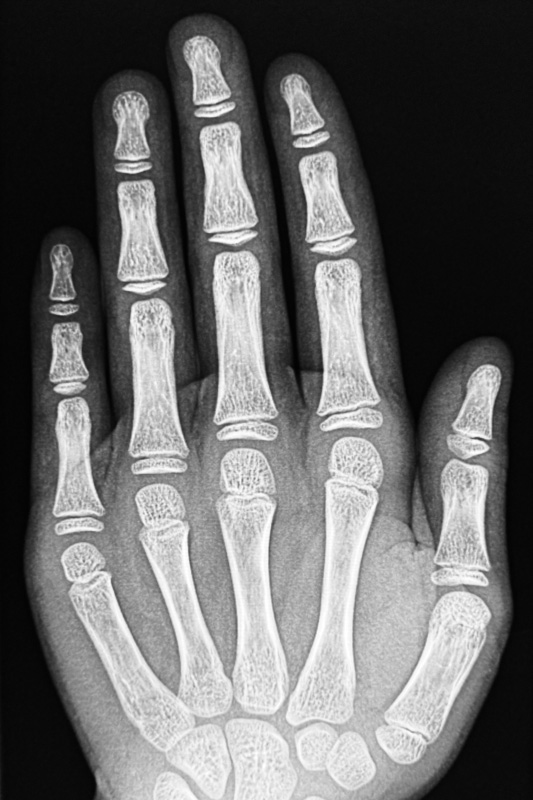

Das erste bildgebende Verfahren in der Medizin hat sich nicht nur seit mehr als 100 Jahren bewährt, sondern stets weiterentwickelt und mit der Digitalisierung ein zukunftsweisendes Niveau erreicht. Hier bei uns am Raschplatz setzen wir konsequent auf die hochmodernen digitalen Techniken, die für uns längst Standard sind und vielfältigste Vorteile bieten.

Das moderne Röntgen steht für eine exzellente Darstellung und Beurteilung von Erkrankungen z.B. im Bereich des Brustkorbs und Bauches oder auch bei Verletzungen des Skelettsystems.

• Vollkommen schmerzfrei und unbemerkt dringen Röntgenstrahlen durch den Körper des Patienten.

• Die digitale Radiografie macht die Bilder in kürzester Zeit auf dem Bildschirm sichtbar.